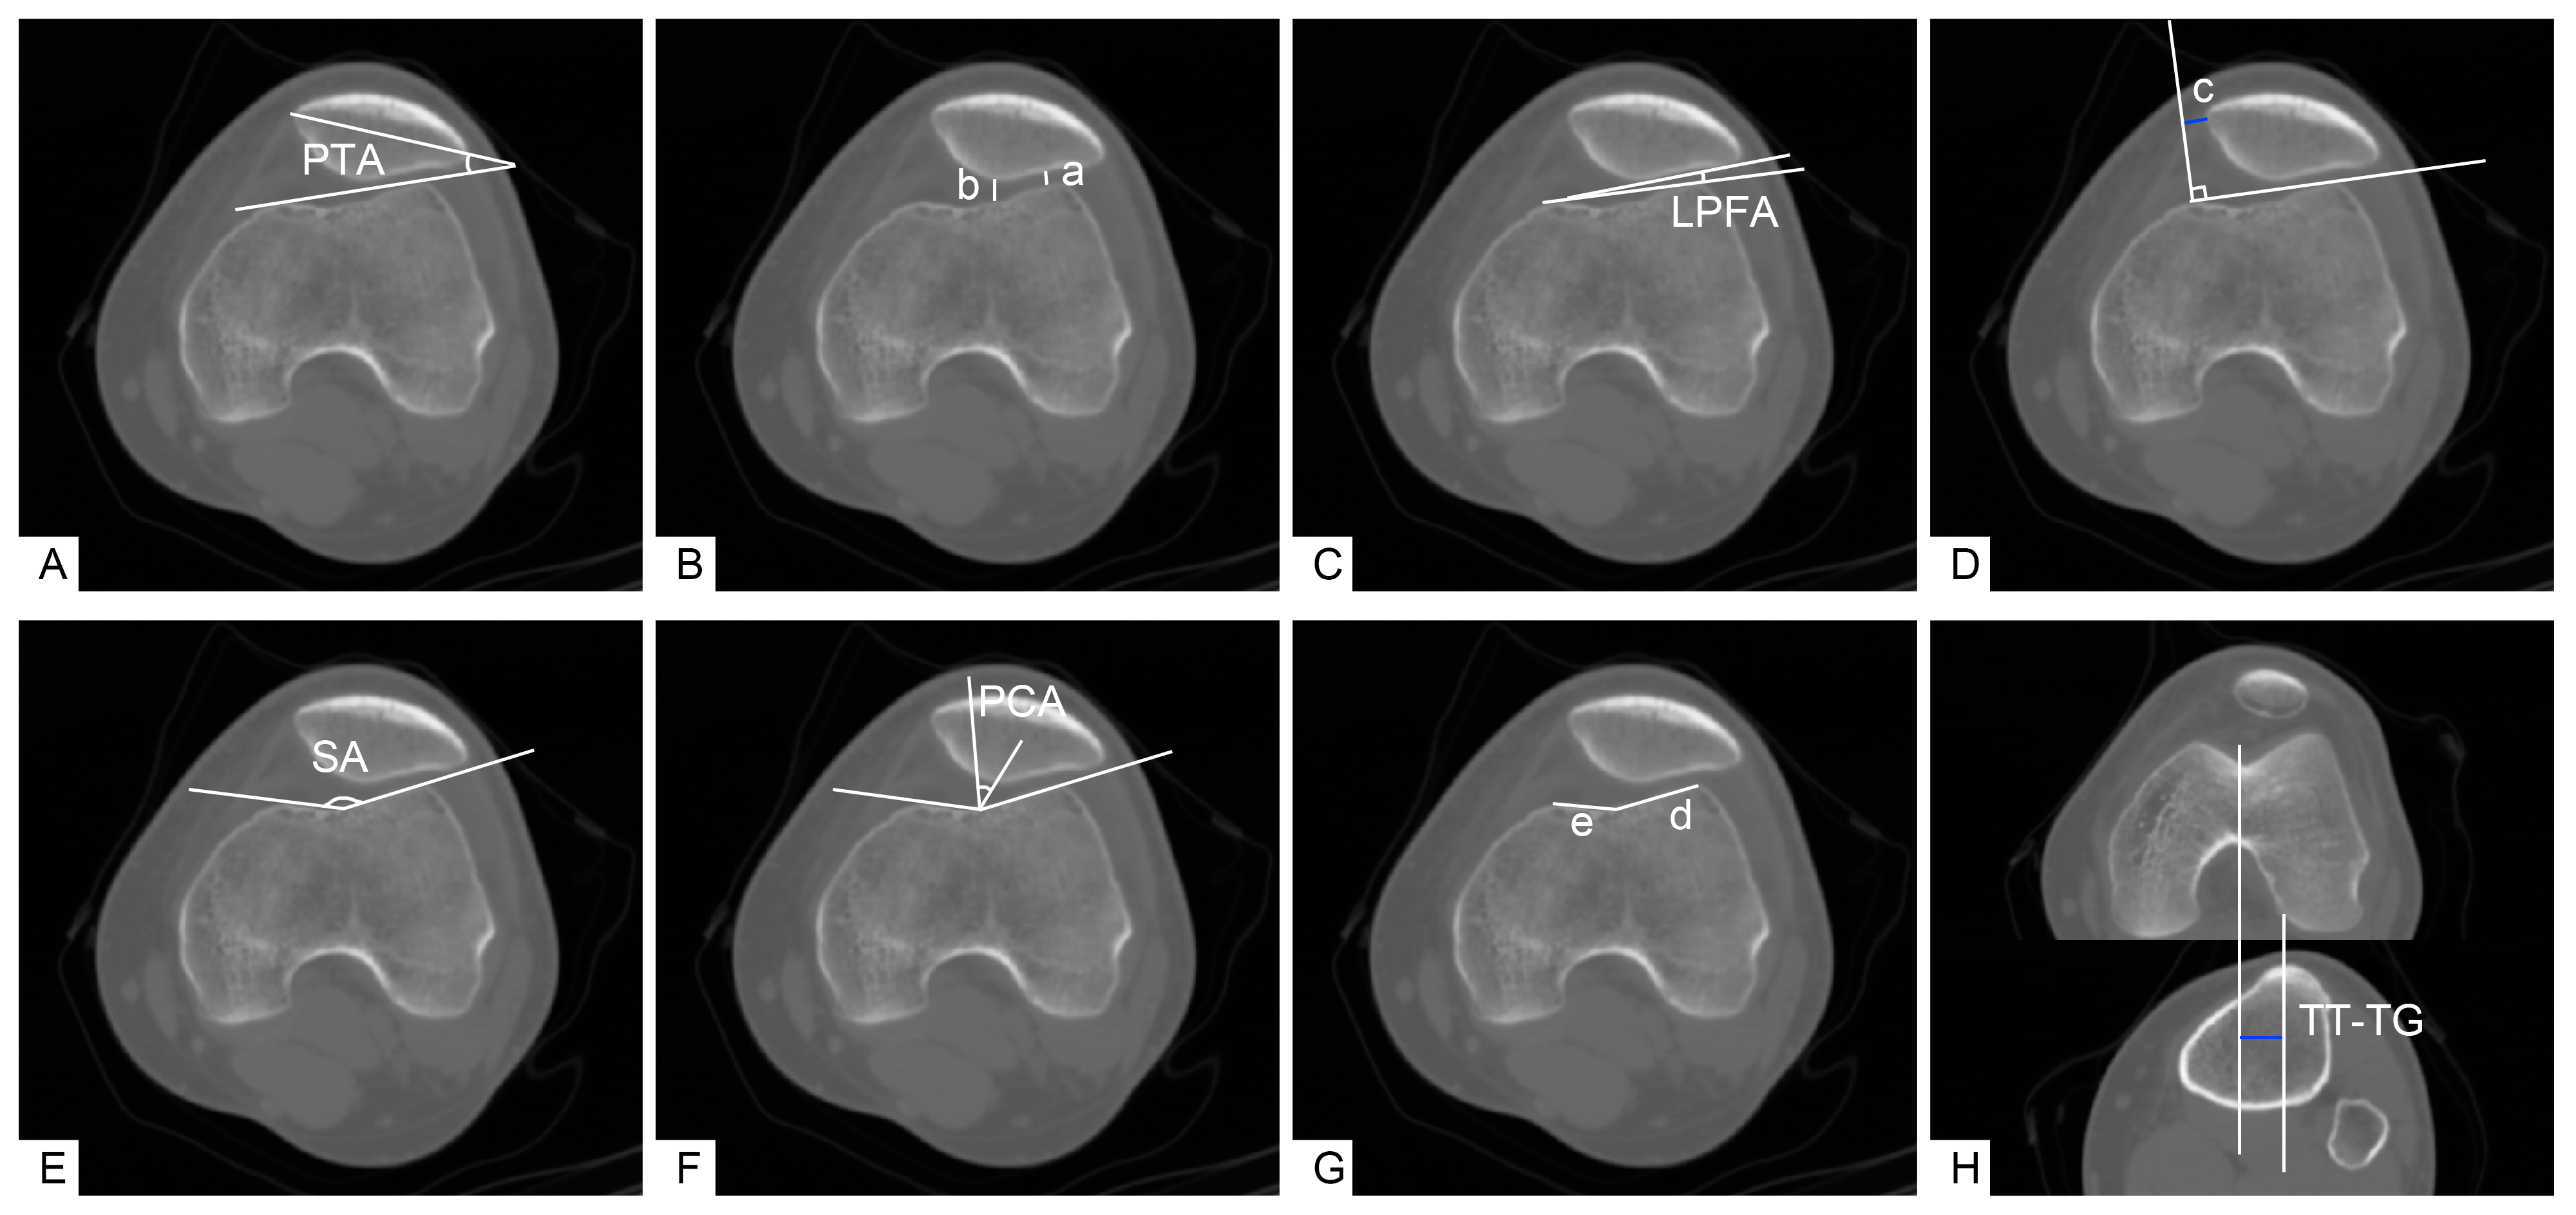

Imaging indicators for the routine evaluation of patellofemoral instability (axial CT scan) (Figure 2) were as follows. First, patellar tilt angle (PTA): the angle between the line connecting each of the highest points of the medial and lateral femoral condyles and the transverse axis of the patella [11]. Second, patellofemoral index (PFI): the ratio of the narrowest width of the medial patellofemoral joint space (b) to the narrowest width of the lateral patellofemoral joint space (a); the normal value is <1.6 generally when evaluating the degree of patellar tilt and subluxation [6]. Third, lateral patellofemoral angle (LPFA): the angle between the tangent line of the lateral articular surface of the patella and the line connecting each of the highest points of the medial and lateral femoral condyles. Under normal conditions, the opening of this angle should be outward (set as a positive number). If the opening was inward (set as a negative number) or the two lines were parallel, then this revealed the occurrence of lateral patellar tilt [12]. Fourth, lateral patellar displacement (LPD): the length between the vertical line of the line connecting each highest point of the medial and lateral femoral condyles from the highest point of the medial femoral condyle (c) and the inner edge of the patella. The inner edge of a normal patella should be close to the vertical line, on or beyond the vertical line (set as a negative number); significant deviation from the vertical line indicated the lateral displacement of the patella (set as a positive number) [12]. Fifth, sulcus angle (SA): the angle between the line connecting the lowest point of the femoral trochlear groove and each of the highest points of the medial and lateral trochlear articular surfaces. An angle > 145° was considered as femoral trochlear dysplasia (FTD) [13]. Sixth, patellar congruency angle (PCA): the angle between the line connecting the lowest point of the femoral trochlear sulcus and the lowest point of the patellar crest and the bisector of the SA made on the axial image of the patella [14]. Seventh, sulcus lateral facet ratio (SLFR): the ratio of the lateral articular surface of the femoral trochlear joint (d) to the medial articular surface of the femoral trochlear joint (e); a value > 2.5 was regarded as FTD [15]. Finally, tibial tubercle-trochlear groove distance (TT-TG): the mediolateral distance between the highest point of the tibial tuberosity to the deepest point of the trochlear groove in line with the posterior condylar axis. A TT-TG > 2 cm served as a sign of a pathological lateral position of the tibial tubercle (a surgical indication of tibial tubercle displacement) [16].

Figure 2. Measurement of assessment indices for patellofemoral instability in knee CT. (A) Patellar tilt angle (PTA): the angle between the line connecting each of the highest points of the medial and lateral femoral condyles and the transverse axis of the patella. (B) Patellofemoral index (PFI): the ratio of the narrowest width of the medial patellofemoral joint space (b) to the narrowest width of the lateral patellofemoral joint space (a). (C) Lateral patellofemoral angle (LPFA): the angle between the tangent line of the lateral articular surface of the patella and a line connecting each of the highest points of the medial and lateral femoral condyles. (D) Lateral patellar displacement (LPD): the length between a vertical line connecting each of the highest points of the medial and lateral femoral condyles from the highest point of the medial femoral condyle (c) and the inner edge of the patella. (E) Sulcus angle (SA): the angle between the line connecting the lowest point of the femoral trochlear groove and each of the highest points of the medial and lateral trochlear articular surfaces. (F) Patellar congruency angle (PCA): the angle between a line connecting the lowest point of the femoral trochlear sulcus and the lowest point of the patellar crest and the bisector of the SA made on the axial image of the patella [14]. (G) Sulcus lateral facet ratio (SLFR): the ratio of the lateral articular surface of the femoral trochlear joint (d) to the medial articular surface of the femoral trochlear joint (e). (H) Tibial tubercle-trochlear groove distance (TT-TG): the mediolateral distance between the highest point of the tibial tuberosity to the deepest point of the trochlear groove in line with the posterior condylar axis.